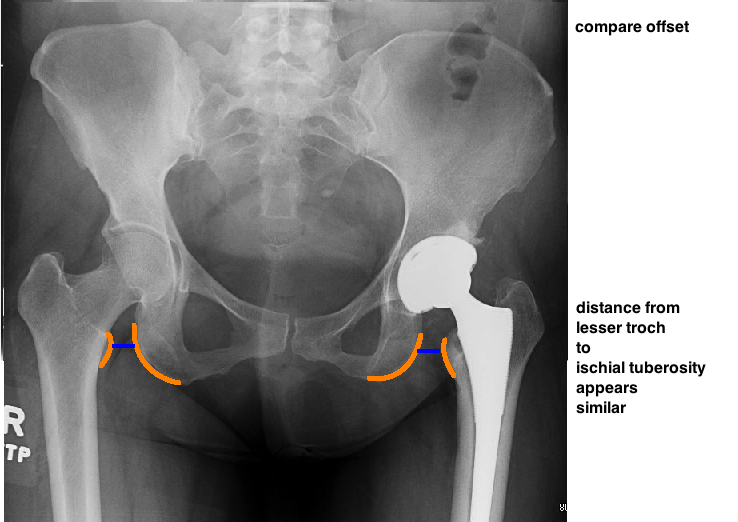

POST-OP EVALUATION

START BY EVALUATING CUP PLACEMENT

THEN EVALUATE STEM PLACEMENT.